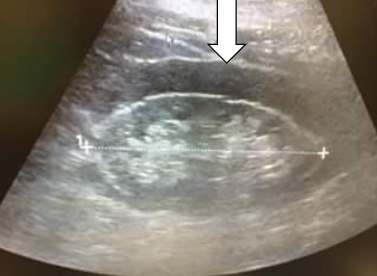

name that pathology -Dilation of the renal pelvis, calyceal structures, and infundibula by urine -Obstruction can be either intrinsic or extrinsic -Sonographic “hallmark” - splaying, spreading, or ballooning of the central echo complex -Dilated ureter helpful in differentiation

HYDRONEPHROSIS

28

hydronephrosis ratings Mild (aka pelvicaliectasis) ◦ dilatation of the renal pelvis with or without dilatation of the calyces (pelvicalyceal pattern is retained) ◦ Dilatation may also be noted in the extrarenal pelvis ◦ no parenchymal atrophy Moderate ◦ moderate dilatation of the renal pelvis and calyces ◦ blunting of fornices and flattening of papillae ◦ mild cortical thinning may be seen Grade 4 (severe) ◦ gross dilatation of the renal pelvis and calyces, which appear ballooned ◦ loss of borders between the renal pelvis and calyces ◦ renal atrophy seen as cortical thinning